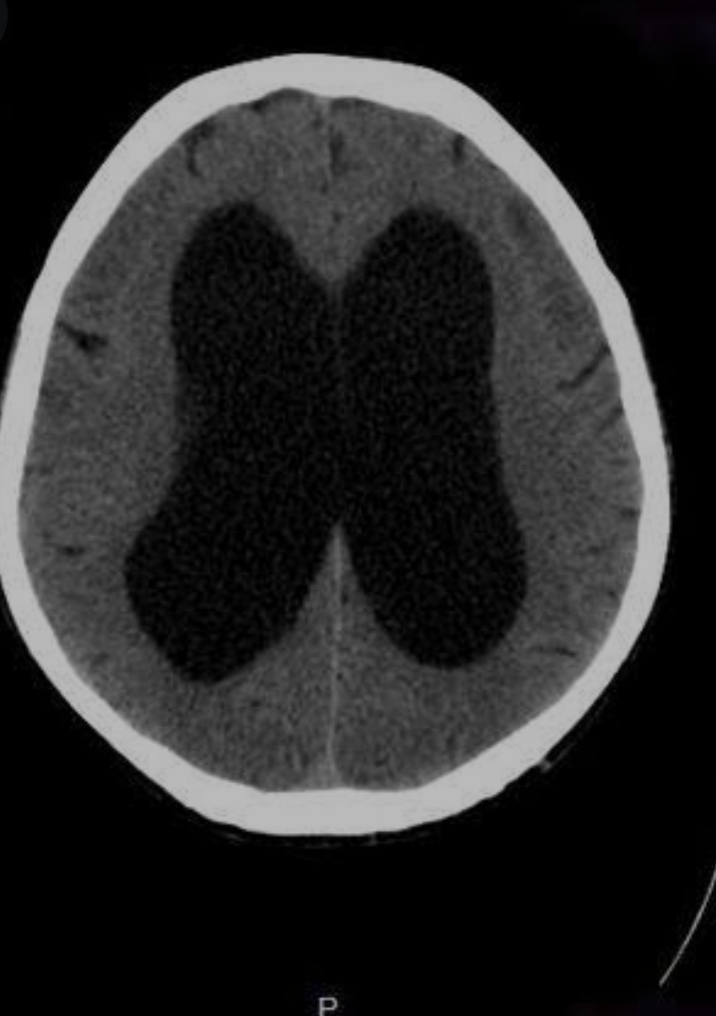

متلازمة ( آدم حكيم ) أو الإستسقاء المخي دون إرتفاع ضغط المخ هي أحد الأمراض التي تؤثر علي المخ في كبار السن وتعد تحديا حقيقيا لجراحي المخ والأعصاب في التشخيص والعلاج.

وجود هذه الأعراض مع تغيرات في الأشعة المقطعية علي المخ يشير بشدة إلي متلازمة ( آدم حكيم) والتي تستجيب بشدة للجراحات المخفضة لضغط المخ (بالرغم من أن ضغط المخ لا يكون مرتفعا) مثل تركيب الصمام المخي البريتوني.